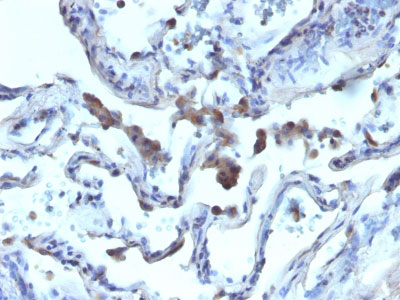

Formalin-fixed, paraffin-embedded human Prostate Carcinoma stained with AMACR / p504S Rabbit Polyclonal Antibody.

Formalin-fixed, paraffin-embedded human Lung Carcinoma stained with AMACR / p504S Rabbit Polyclonal Antibody. |

This antibody recognizes a protein of 54kDa, which is identified as AMACR, also known as p504S. It is an enzyme that is involved in bile acid biosynthesis and ? ?-oxidation of branched-chain fatty acids. AMACR is essential in lipid metabolism. It is expressed in cells of premalignant high-grade prostatic intraepithelial neoplasia (HGPIN) and prostate adenocarcinoma. The majority of the carcinoma cells show a distinct granular cytoplasmic staining reaction. AMACR is present at low or undetectable levels in glandular epithelial cells of normal prostate and benign prostatic hyperplasia. A spotty granular cytoplasmic staining is seen in a few cells of the benign glands. AMACR is expressed in normal liver (hepatocytes), kidney (tubular epithelial cells) and gall bladder (epithelial cells). Expression has also been found in lung (bronchial epithelial cells) and colon (colonic surface epithelium). AMACR expression can also be found in hepatocellular carcinoma and kidney carcinoma. Past studies have also shown that AMACR is expressed in various colon carcinomas (well, moderately and poorly differentiated) and over expressed in prostate carcinoma.